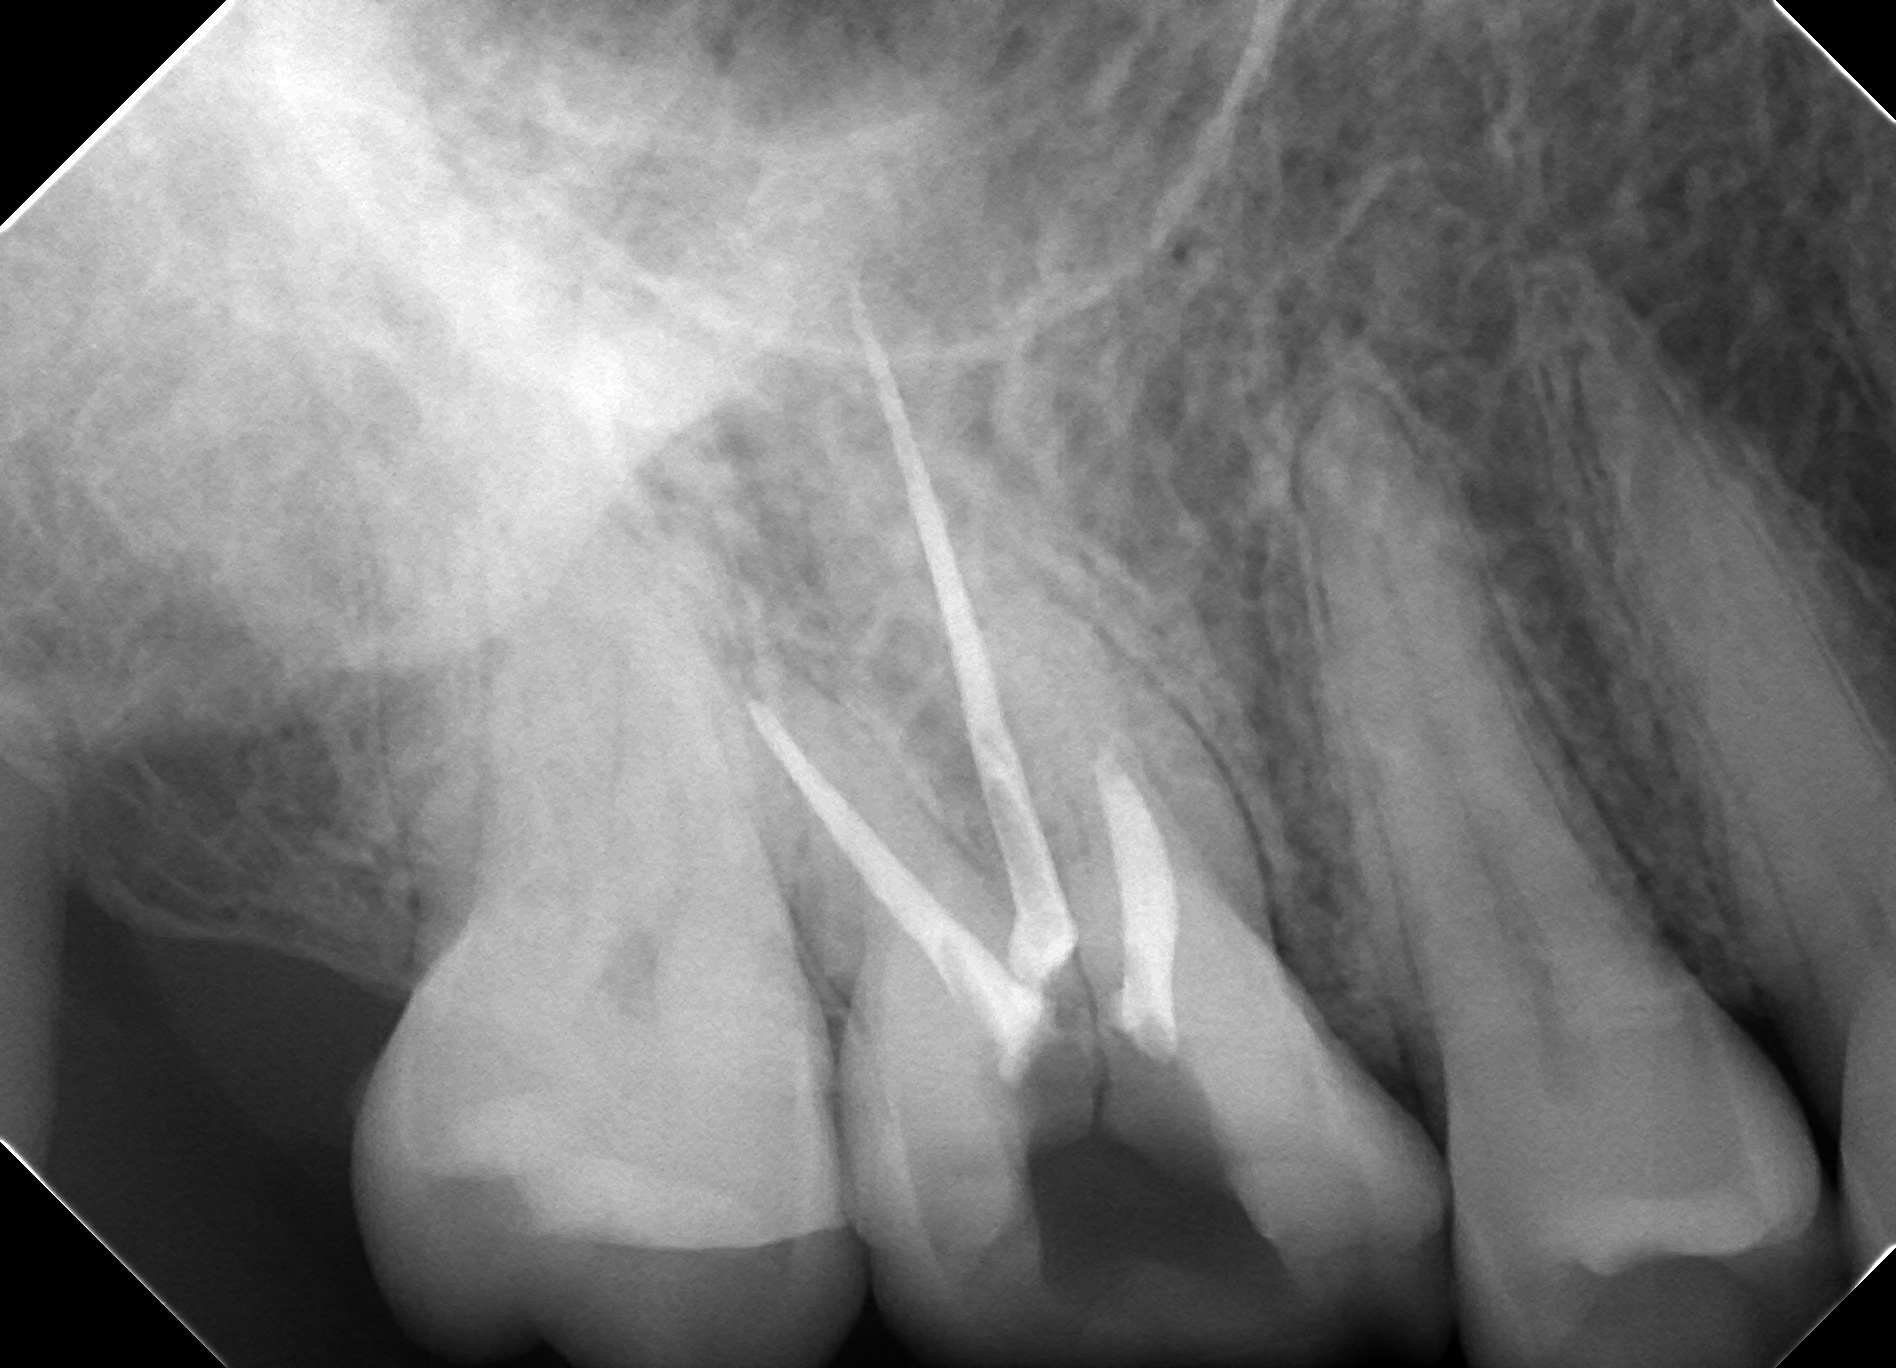

歯牙移植のコツ

今回は歯牙移植についてそのコツをご説明したいと思います。 欠損歯牙補綴手段として最近はインプラントが発達しておりますが、歯牙移植術はインプラントと違って歯根膜まで再生できるため、より生理的状態に近い形で咬合を回復できます […]